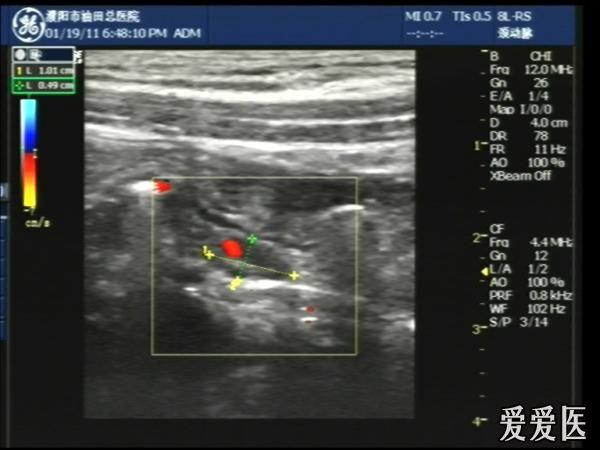

超声检查:于下腹部可见“双环征象”,双环重叠长约6mm,检查期间观察可见肠蠕动;CDFI:未见明显异常血流信号。

超声提示:下腹部双环征,考虑肠套叠可能,请结合临床